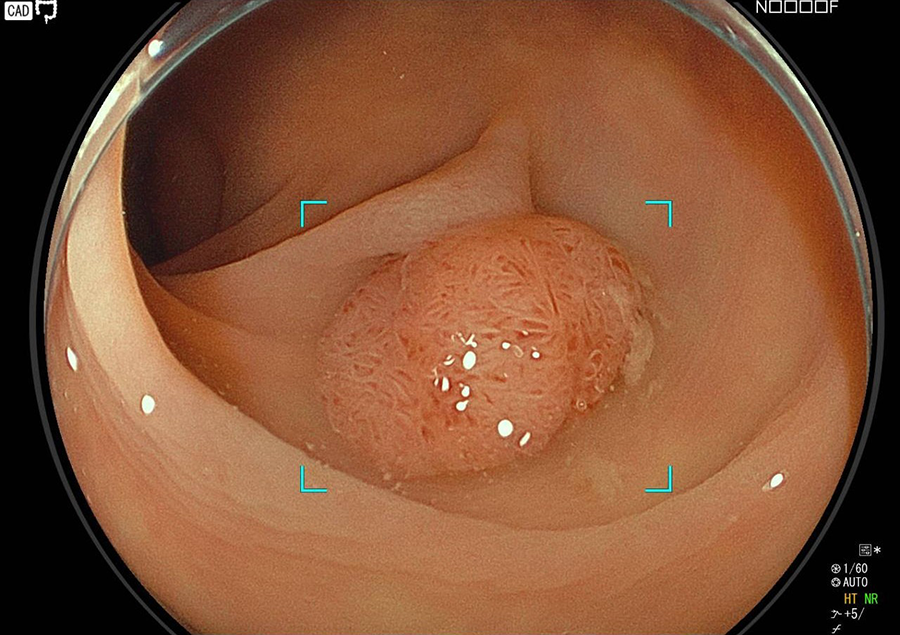

大腸カメラはポリープやがんの発見と診断に、最も精度の高い検査法です。

近年、大腸がんが急速に増加していますが、がんの芽となるポリープ(腺腫)、一部の早期がんは、大腸カメラによる内視鏡治療で完治させることが可能です。

そこで当院では大腸カメラ検査時にポリープや早期がんが発見された場合は、可能な限り積極的にその場で切除しております。